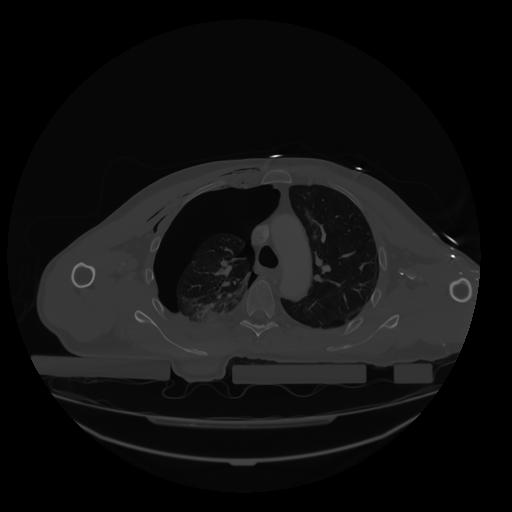

28 CUERPO,CE,Vol,2.0,CUERPO,,